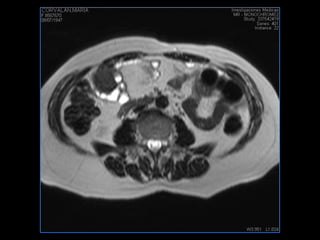

PROTOCOLO abdomen COR T2, AXIAL supresion grasa AX T1 +SAG T2  CON   GADOLINIO :  COR T1+AX T1(DIN) SAT: NO  FASE: RL THK: 6MM  COIL:  GAP: (FACTOR 1.4) 2MM FOV: 40 CM NEX:2 SINCRONIZACION RESPIRATORIA EN 3 O 4 CICLOS ALE